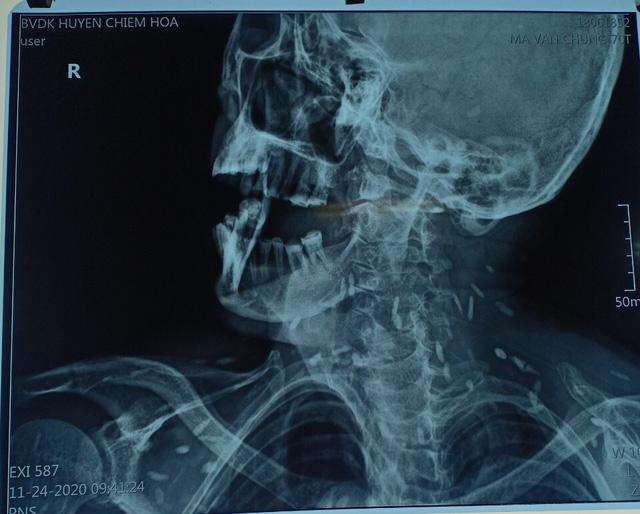

Hình ảnh chụp X-quang nam bệnh nhân 70 tuổi mắc bệnh kén sán toàn thân. Ảnh: TTYT huyện Chiêm Hoá

BS.ThS Phạm Chí Cường cho biết: "Cụ ông nhập viện vì đau răng, nhai kém và khó há miệng. Khi chụp X-quang thì kết quả là viêm quanh cuống răng. Thế nhưng, hình ảnh chụp thì cho ra rất nhiều sán, kén sán, các ổ vôi hoá nhu mô não do sán".

Cũng theo BS Cường, khai thác bệnh sử thì bệnh nhân mới cho hay là sở thích ăn gỏi sống. Mặc dù phát hiện bản thân mắc bệnh kén sán đã 4 năm nhưng không điều trị. Do quá đau vùng hàm dưới và sưng nền má phải nên mới phải đến bệnh viện để khám.